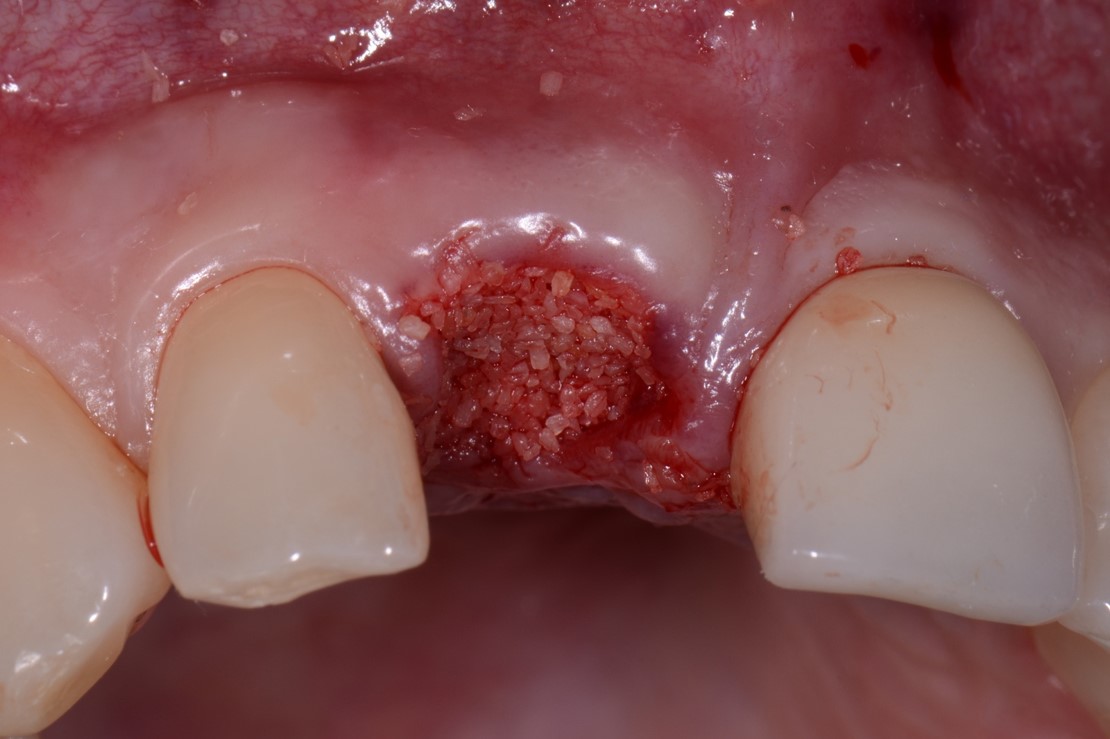

Fig 21. Bone graft material enhanced with growth factor was placed.

Figure 21

Fig 22. The site was protected by the extra height of soft tissue, along with a membrane.

Figure 22